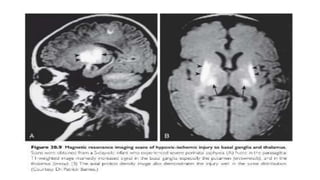

• Certain distributional patterns of brain injury which may be typical of

HI injury are:

- Injury to deep gray nuclei especially the posterior putamen and

anterolateral thalami

• Lesions associated affecting b/l basal ganglia and thalami that are detected

by MRI in the first weeks of life have been associated with poor neurologic

outcomes and death